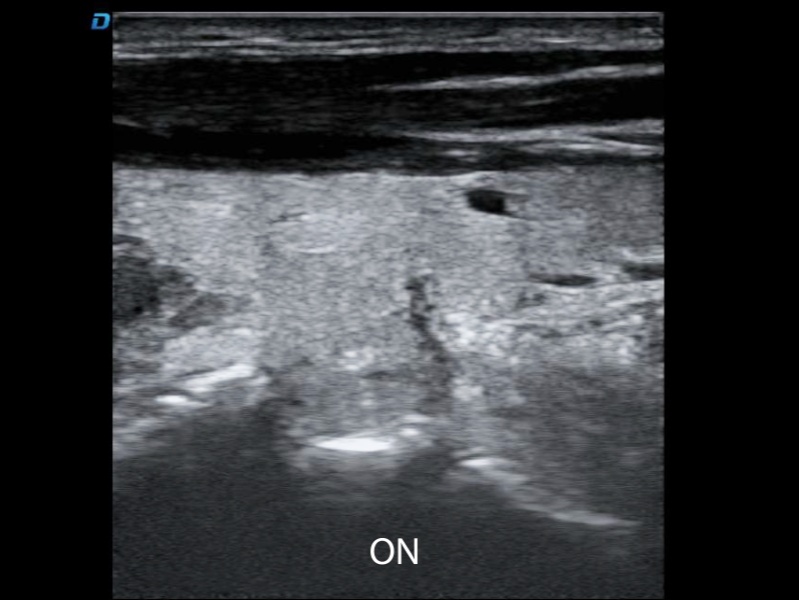

DW-L3S は、豊富な画像機能と優れた鮮明な画像により、腹部、産婦人科、血管、筋骨格系およびその他の一般医学の一般的な診断ニーズを満たす臨床アプリケーションを可能にします。

DW-L3S超音波診断システムは、強力な技術コアに基づいており、B超音波、カラードプラ、指向性エネルギードプラなどのイメージング機能をサポートしています。内蔵のインテリジェント測定ソフトウェアパッケージは、一般的な測定機能評価や血管パラメータ分析などの臨床モジュールをカバーしており、正確なイメージングと効率的なワークフローの有機的な一体性を真に実現しています。